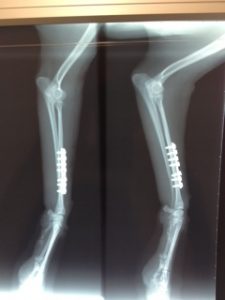

2013.10.08

橈尺骨骨折